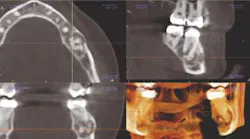

The second major change comes in interpreting the images. You have to take the time to understand the anatomy, even if you are using a machine that allows for focused volume views, such as the CS 9300 (Carestream Dental), which you're familiar with. Take the time to learn the science, the 3-D radiographic anatomy and radiographic interpretation, radiation dosimetry, and 3-D imaging.

Above: Images from the Carestream Dental CS 9300